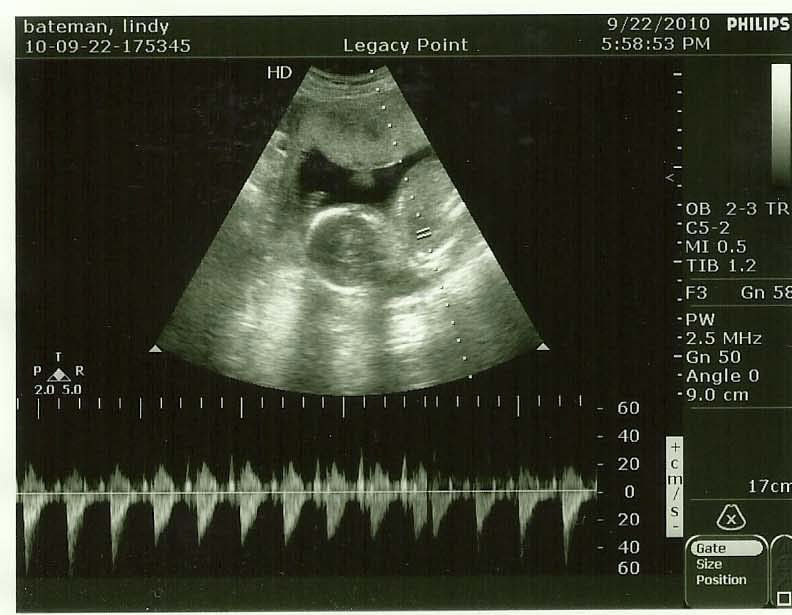

If you didn't know already, we're going to have a BOY. Yes, we found out back on September 22. I have been a huge slacker in life in general. So now you know. The baby showed off his stuff the second she put the thing on me.